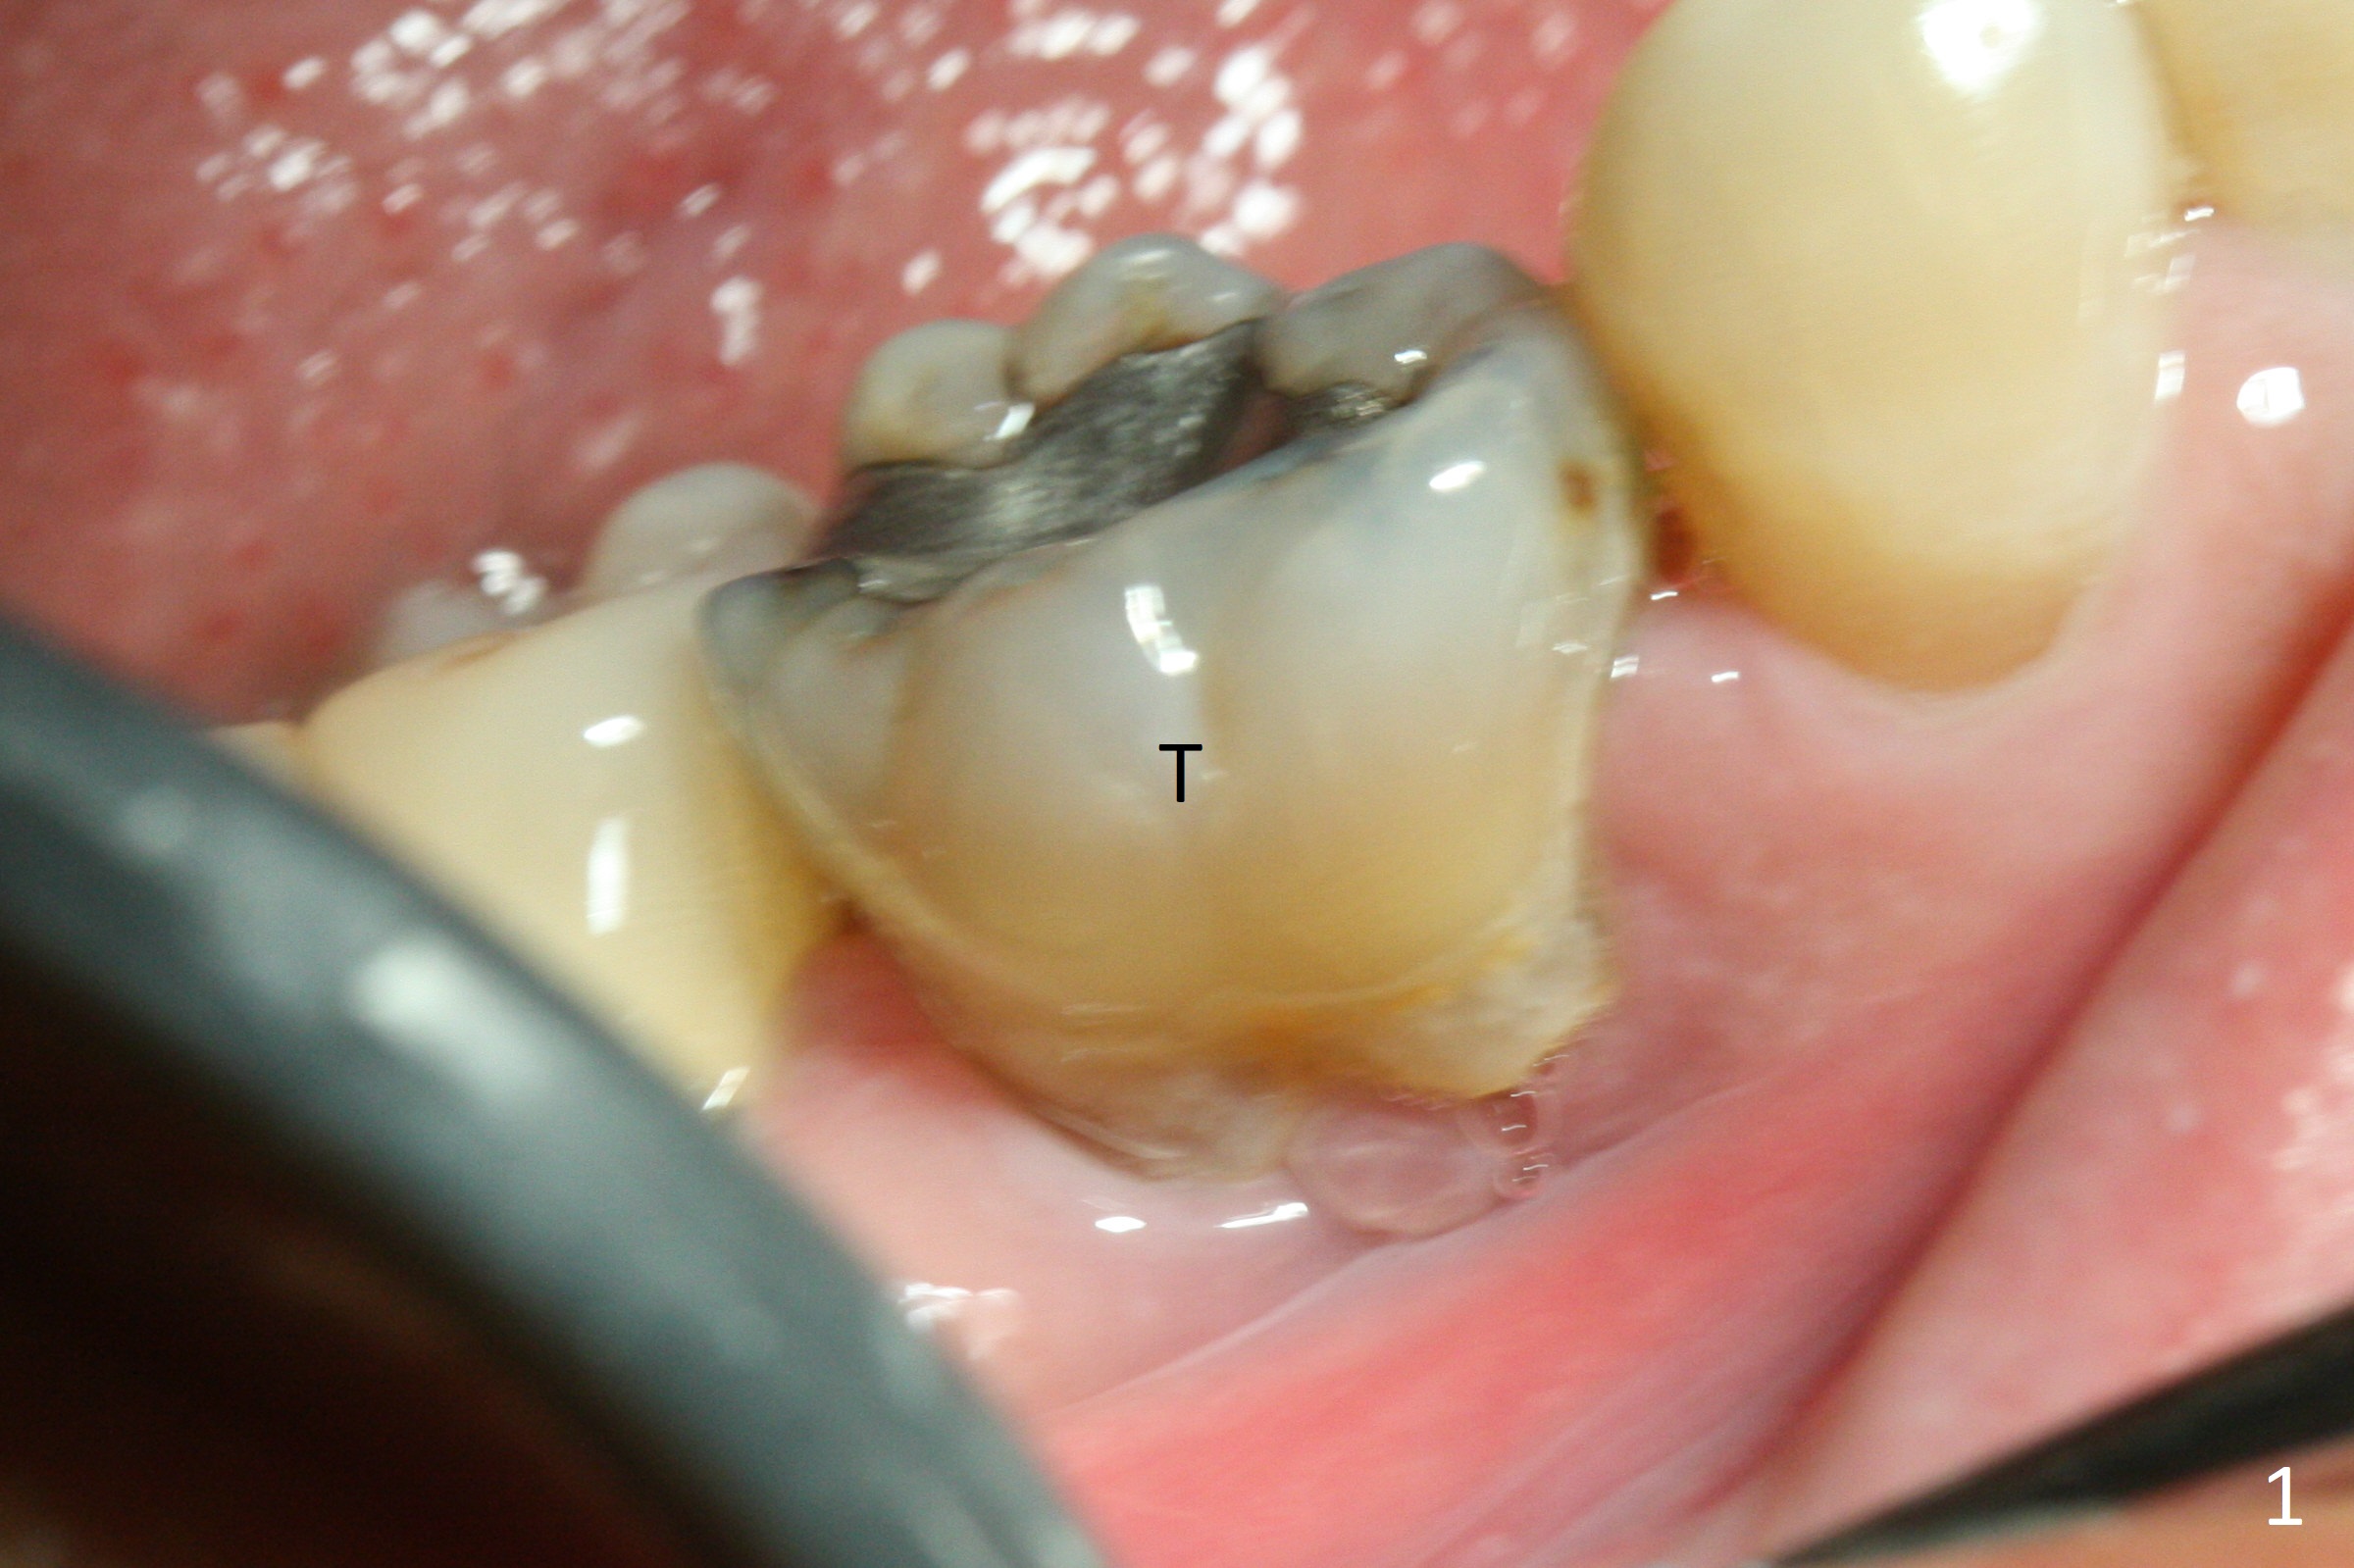

The retained deciduous tooth (lower right 2nd molar, Fig.1 T) has buccal apical infection and recession. After extraction, the initial depth of osteotomy is 11 mm over the flat socket bottom (Fig.2) without visible Mental Loop. Following 3.8 mm Magic Drill for 11 mm, a 4x11 mm dummy implant is placed partially due to hard bone; it appears that the apical osteotomy (Fig.3 yellow outline) overlaps the Mental Loop (red dashed line). For safety, a 4x9 mm IBS implant is placed with insertion torque 40 Ncm; a 5x5.7(4) mm abutment is immediately placed for an immediate provisional to cover the large socket and keep Vera graft in place (Fig.4 *). There is no postop paresthesia, probably due to the fact that the osteotomy is lingual to the Mental Loop. The provisional remains in place 7 days postop; its margin (Fig.5 arrow) covers the socket. The margin of the provisional is trimmed 1 month postop. Impression is taken nearly 3 months postop (Fig.6). The buccal plate looks atrophic 3 months postop (Fig.7 (immediately before cementation)), although there is no sign of periimplantitis. In the future, insert the immediate provisional inside of the buccal gingiva to make the buccal gingiva look bulky instead of buccal to it (Fig.5). The second drawback of placing an implant at the deciduous tooth area is that the crown is wide mesiodistally if orthodontic treatment is not rendered. Although there is lower anterior crowding, the patient declines orthodontic treatment. The bone density around the implant increases 7 months post cementation (Fig.8 *). The higher density bone seems to extend coronally 1 year 7 months post cementation (Fig.9). The dense bone apparently extends toward the abutment as well 3 years 5 months post cementation (Fig.10 curved arrows).